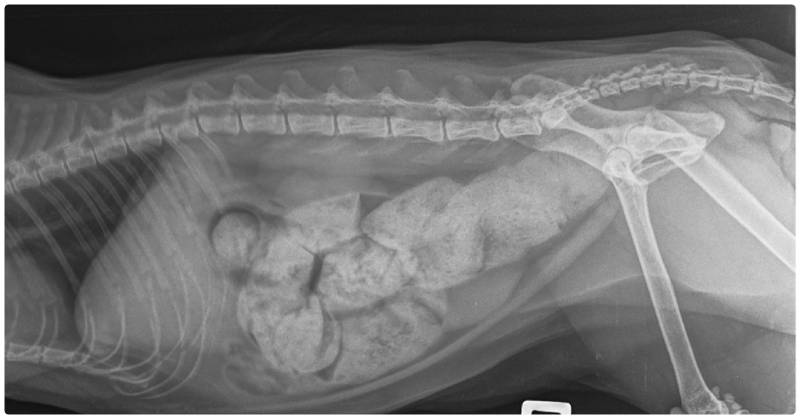

Constipation

constipation cat or megacolon cat xray film

Image Credit: Vetlife, Shutterstock

When a cat doesn’t have enough moisture in their system, they can become constipated. If your cat is straining to poop and hasn’t had many bowel movements, they are possibly constipated and dehydrated.  This requires assessment by your vet urgently because a back-up of feces can become very painful and lead to other, more long term problems.